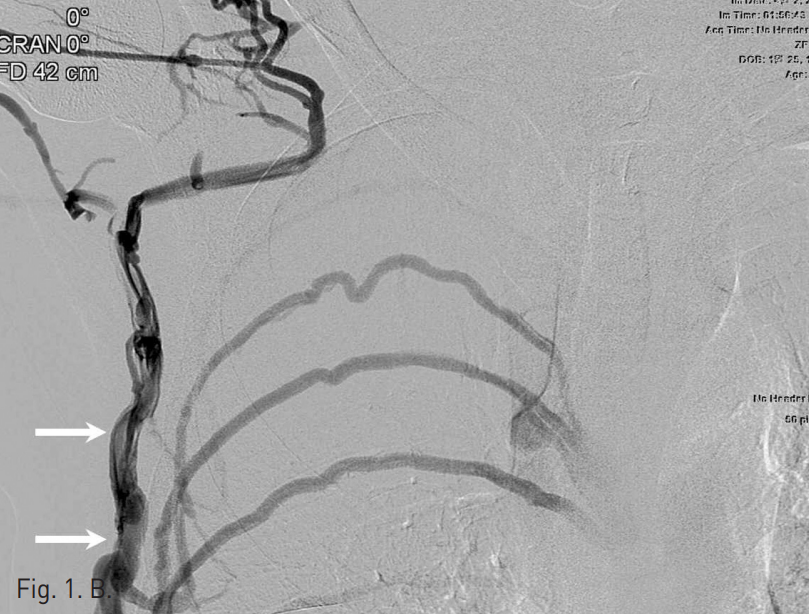

Prone position하에 22G 정맥주사용 바늘로 우측 외흉정맥 천자를 먼저 시도하였으나 조영제의 혈관 외 유출이 발생하여 실패하였음. 초음파 유도하에 우측 7번째 늑간정맥을 micropuncture needle (Cook, Bloomington, USA)로 천자하였고, 투시 유도하에 조영제를 주입하여 늑간정맥을 확인한 다음(Fig. 2) 0.018-inch hairy wire를 삽입하였음. Hairy wire를 거치한 상태에서 5F coaxial dilator를 통해 늑간정맥 조영술을 시행했을 때 기정맥을 통해 심장으로 조영제가 유입되었고(Fig. 3), hairy wire를 우심방까지 전진하였음. 늑간정맥 내로 삽입한 6F peel-away sheath내로 6F dual lumen PICC 카테터 (Vaxel, Navilyst Medical, USA)를 삽입하여 말단부가 우심방 내에 위치하도록 하고 시술을 마쳤음(Fig. 4).

Fig. 2

After puncturing the right seventh intercostal vein under ul trasound guidance, the location of needle tip in the vein is confirmed by injecting contrast medium.